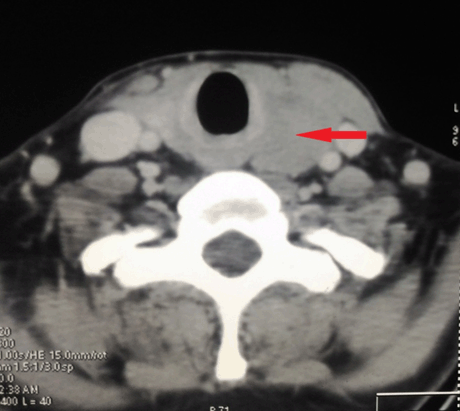

IA 40-year-old male with history of hypothyroidism, taking tab levothyroxine 100 mg once daily since one year presented to our hospital with the presenting complaint of a swelling in left side of neck, with progressive increase in size since last two months. On examination, a diffuse non tender lump measuring 6×3 cm in root of left side neck, moving with deglutition was noted with no palpable lymphadenopathy elsewhere. Serum T3, T4 and TSH levels were within normal limits. All other routine blood investigations were normal. Ultrasonography (USG) of neck showed mixed echogenic mass lesion in left lobe thyroid measuring 56x29 mm. Ultrasonography guided fine-needle aspiration cytology from the left lobe of thyroid lesion showed lymphoid large mononuclear cells. Trucut biopsy from the left thyroid lobe lesion was suggestive of non-Hodgkin’s lymphoma as lymphoid tissue with diffuse medium to large sized atypical cells with prominent round nucleoli and condensed chromatin with scanty cytoplasm and mitotic figures were present (Figure 1). Immunohistochemical analysis was reported as CD20 strongly positive, MIB-1 labeling index 60–65%, CD3 negative, CD5 negative, CD10 negative, CD23 negative, cycline D1 negative and Pan-Cytokeratin negative, suggestive of diffuse large B cell lymphoma (DLBCL) thyroid (Figure 2). The PET-CT scan showed FDG avid hypodense mass lesion involving the left lobe of thyroid gland measuring 63x38x31 mm with SUV Max 31.11 with no evidence of other abnormal lesion in the body (Figure 3). Bone marrow aspirate and biopsy were normal. Based on these investigations, final diagnosis was non-Hodgkin’s lymphoma-Thyroid (DLBCL, stage IEA).

Figure 3: Axial view of contrast enhanced computed tomography scan of neck showing a large hypodense lesion (size max. 63 mm) in left lobe of thyroid.